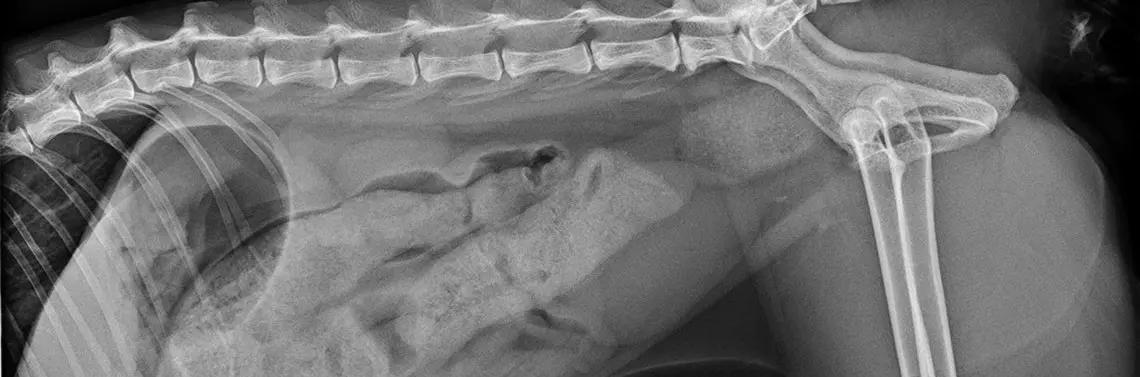

Wykonano zdjęcia rent...